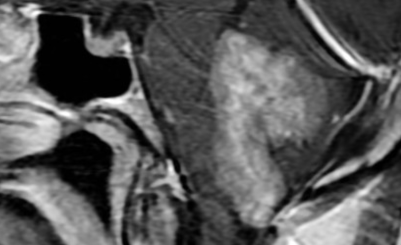

- Tumeur de l’Angle Ponto-Cérébelleuse

- Schwannome vestibuliare (Neurinome accoustique)

- Méningiome

- Kyste épidermoide